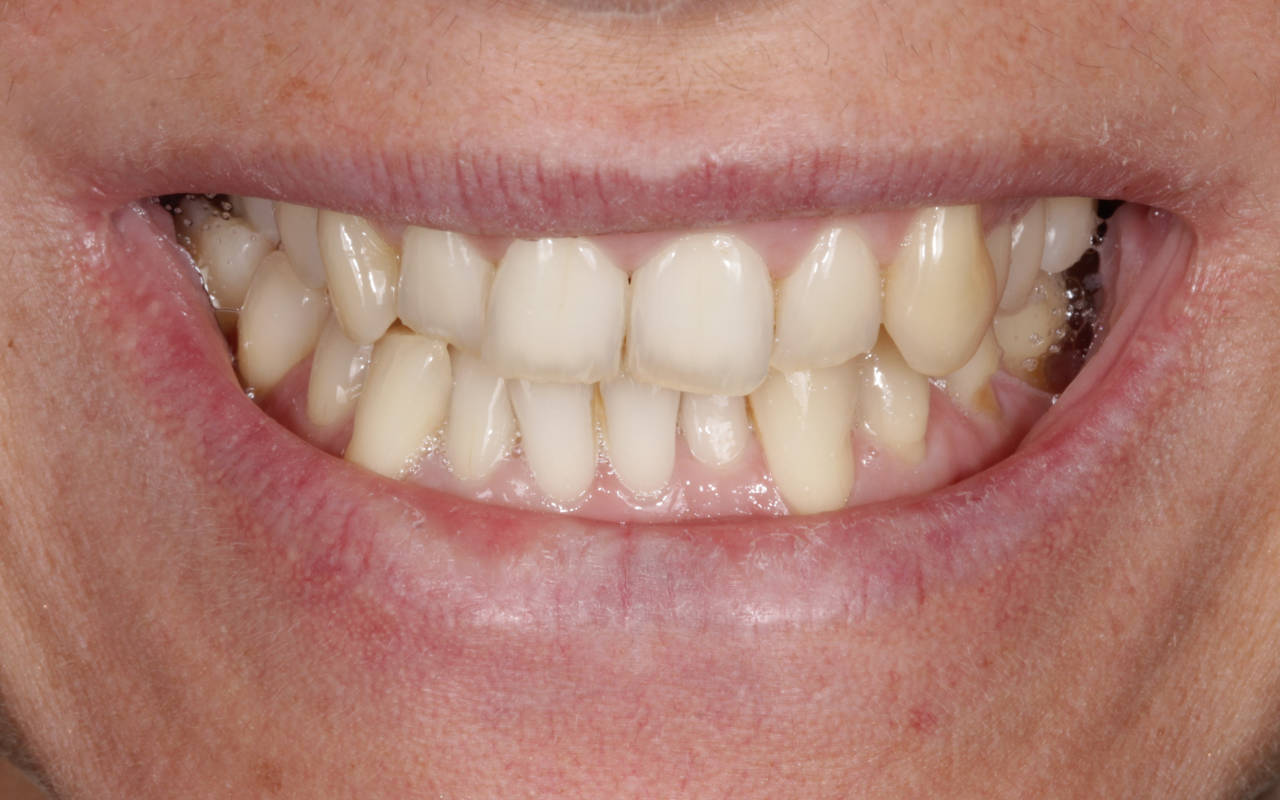

A harmonização do sorriso fez toda a diferença nes